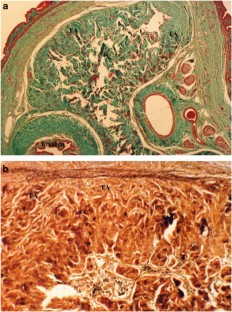

Several biodegradable materials have been experimented for penile enhancement, but none show the potential for clinical use. This study was designed to use porcine small intestinal submucosa (SIS) augmenting the normal tunica albuginea to increase the functional girth of the rat penis. In all, 20 adult male Sprague–Dawley rats constituted the study population. The animals were divided into two groups: group 1 consisted of the control (n=10) and group 2 (n=10) consisted of rats that underwent penile enhancement by a longitudinal I-shaped incision of the tunica albuginea on both sides, and the dissection of the plane between tunica albuginea and cavernosal tissue was carried out (n=10). The incision was then patched with a 3 × 10 mm2 piece of SIS, using a 6/0 nylon suture material. The penile length and mid-circumference were then measured using a Vernier Caliper before and 2 months after surgery. All rat penises underwent histological examination using Masson's trichome and Verhoff's van Giesen's stain for collagen and elastic fibers. The penile length, mid-circumference and degree of fibrosis score were expressed as mean±s.e. (standard error) and analyzed using a Wilcoxon rank-sum test. A statistical significance was accepted at P-value ⩽0.05. Our results showed similar preoperative penile length and circumference in both groups. However, 2 months after the surgery, the mean penile circumference of the SIS group has grown significantly larger than the control group, while the mean penile length remained unchanged. The histological study of the rat penises revealed minimal amounts of fibrosis under the graft, and the elastic fibers of the graft showed orientation in a circular manner. In conclusion, SIS appears promising for material use in a penile enhancement.